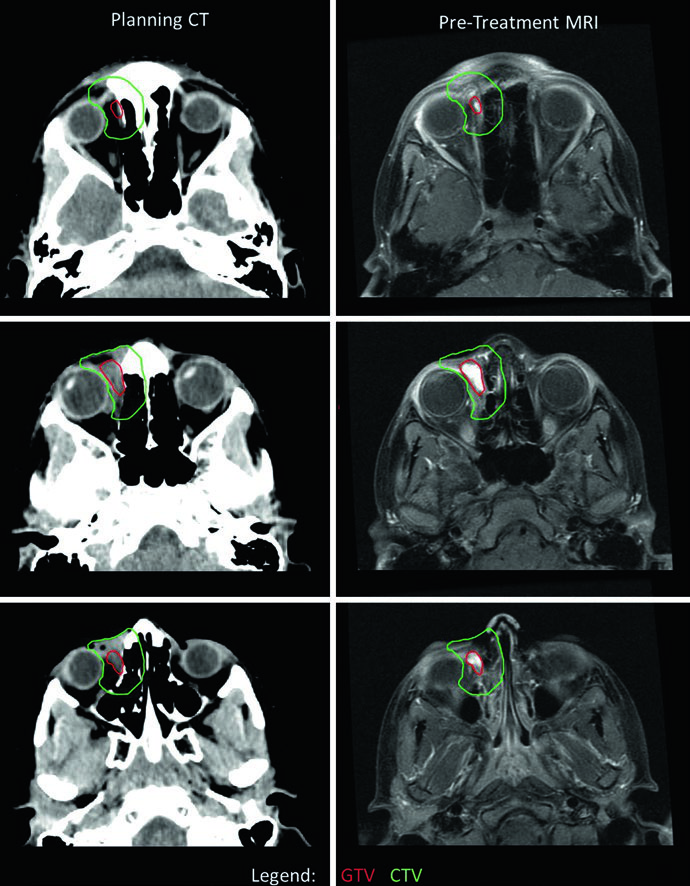

No RMS orbital, o delineamento exige atenção à preservação de estruturas oculares. Neste caso, a CTV se estendeu além da órbita óssea em alguns cortes por suspeita de erosão óssea — em geral, o CTV de RMS orbital não deve exceder os limites da órbita óssea na ausência de erosão. Um desvio lateral do olho direito foi utilizado para otimizar a preservação do cristalino e do nervo óptico. Como o tumor respondeu minimamente à quimioterapia de indução, optou-se por dose única de 50,4 Gy. Se houvesse resposta, seriam utilizados dois níveis: 36 Gy com cone-down para 50,4 Gy. Para comparação com tumores benignos e malignos do SNC que também exigem planejamento cuidadoso ao redor de estruturas oculares, consulte nosso artigo sobre tumores malignos do SNC.

O tipo e frequência de guiamento por imagem determinam a margem CTV-PTV. Muitas instituições utilizam kV diário e consequentemente margens de PTV de 3 a 5 mm. Margens menores podem ser consideradas em cenários com guiamento mais robusto ou proximidade de estruturas críticas — situação frequente em sarcomas de cabeça e pescoço, onde nervos ópticos, tronco encefálico e outras estruturas estão próximas aos volumes-alvo. A simulação por RM pode complementar a TC para fornecer dados de RM na posição de tratamento. Em pacientes mais jovens — geralmente abaixo de 8 anos — sedação ou anestesia diária pode ser necessária. Para planejamento de outros tumores pediátricos no SNC que também requerem imobilização rigorosa, confira nosso artigo sobre tumores cerebrais pediátricos.